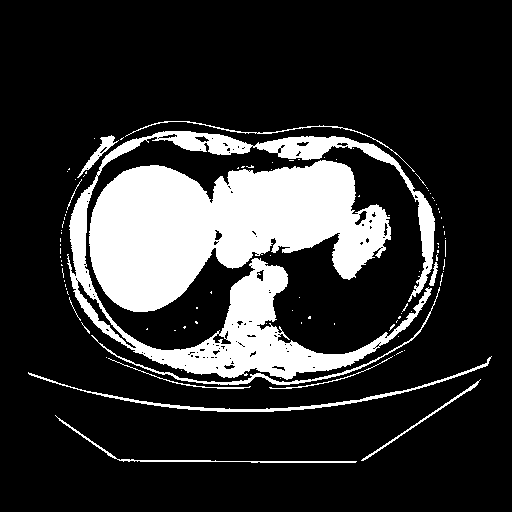

Original NATIVE CT scan (input)

Full window (WL 1023.5, WW 4095 β†’ Low βˆ’1024, High +3071)

Actual HU range: [-1024.0, 3071.0]